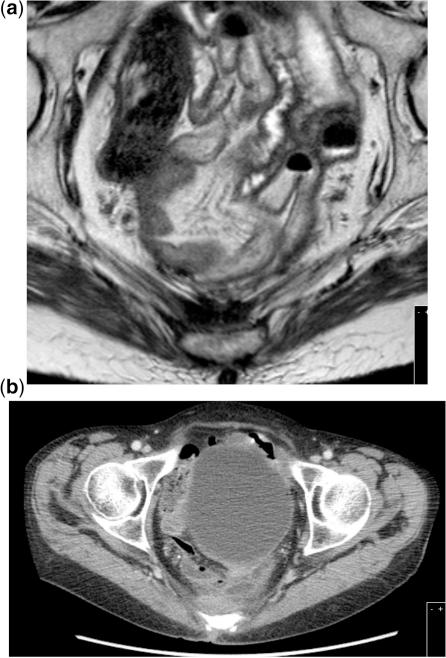

Radical resection is the only potential cure for patients with locally advanced primary and recurrent rectal cancer and is considered curative only when the histologic margins are clear of tumour. Early diagnosis of the disease is essential as it increases the likelihood of a potentially curative resection and prevention of dissemination. Clinical examination, tumour markers and radiologic modalities such as ultrasonography, computed tomography, magnetic resonance imaging and positron emission tomography are routinely used in an effort to accurately stage these patients and provide useful information for the selection of patients for further treatment/management. This review describes the methods of staging patients with locally advanced primary and recurrent rectal cancer prior to surgery emphasizing the role that radiologists have in this process.

根治性切除术是局部晚期原发性和复发性直肠癌患者的唯一潜在治愈方法,只有当组织学切缘无肿瘤时才被认为是治愈性的。早期诊断疾病至关重要,因为这增加了潜在治愈性切除的可能性,并防止了疾病的扩散。临床检查、肿瘤标志物和影像学方式,如超声、计算机断层扫描、磁共振成像和正电子发射断层扫描,通常用于准确分期这些患者,并为进一步治疗/管理的患者选择提供有用的信息。本综述描述了在手术前对局部晚期原发性和复发性直肠癌患者进行分期的方法,强调了放射科医生在这一过程中的作用。